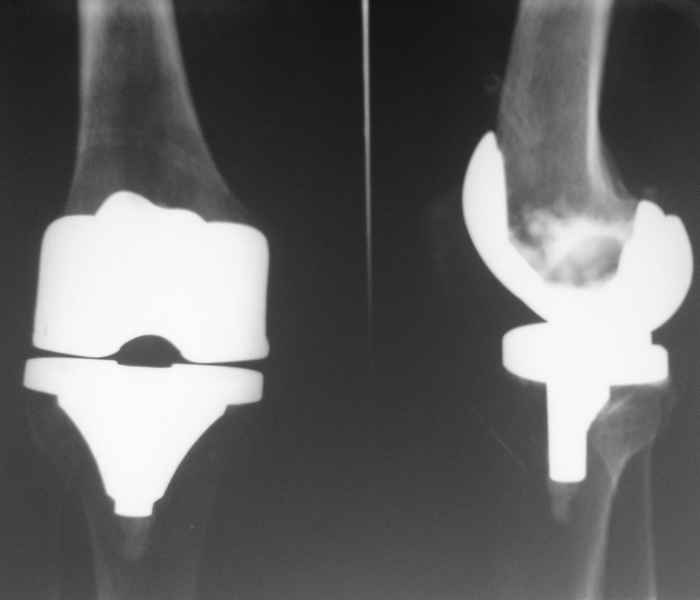

В июле 2007 года выполнена ревизия - полости сустава нет. Капсула сустава имеет толщину от 1 до 1.5 см, собственная связка надколенника имеет толщину до 3 см. Сустав заполнен фиброзно-рубцовой тканью. Компоненты стабильны.

Резецирована капсула, удалены фиброзные ткани из сустава. В области межмыщелковой ямки на бедре обнаружены 2 канала уходящих в мыщелки и проксимально, глубиной до 2 см и диаметром до 1 см. Выскаблены и заполнены синтетическим костным трансплантатом с ванкомицином. Взяты ткани из разных отделов сустава для бак. исследования.

Рана ушита с объемом движений до 70 градусов. По результатам анализов - все стерильно. Как и в посеве крови.

Скорее всего тибиальное плато было не конца резецировано и в задненаружных отделах осталась ступенька. Это привело к тому, что тибиальный компонент завалился на варус.

Можно пойти на повторную ревизию, удалить большеберцовый компонент и поставить его правильно, но как справиться с артрофиброзом?

Надо ли вести случай как нагноение с удалением протеза и установкой спейсера?